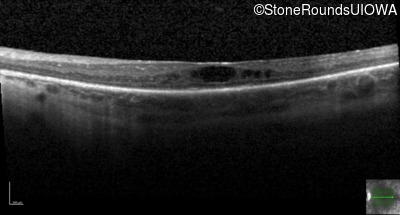

Optical Coherence Tomography - Right - 20/60 -1

Exemplar / OCT Stack